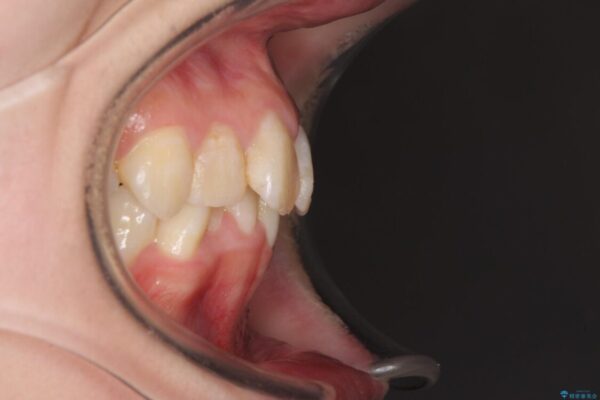

内側に倒れ込んだ歯や下の前歯が隠れてしまうほどの咬み合わせを改善したいとのことで来院された患者様です。

治療前

• デコボコと深い咬み合わせ ワイヤー装置での抜歯矯正 治療前画像